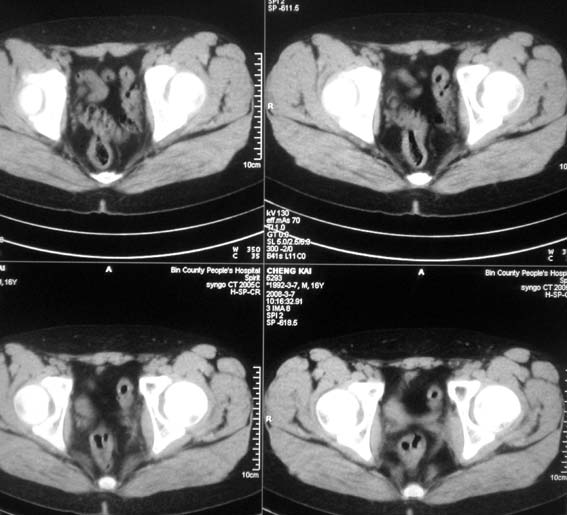

标题: CT12101:髋关节疼痛,请会诊。

男,16岁,髋部疼痛,发育延迟。

考虑:双侧髋臼发育不良性骨病。

双侧髋臼发育不良性骨病

双侧髋臼发育不良性骨病.股骨头早期坏死?

双侧髋臼发育不良性骨病(髋臼窝变浅,髋臼内上缘关节面毛糙)。